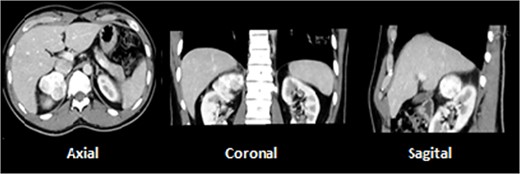

A 73-year-old male with prior history of irritable bowel syndrome presented a 2-week-long abdominal pain, located on the right lower quadrant associated with anorexia and diarrhea, without blood loss or any other symptoms. The CT-scan showed a 9-cm solid preperitoneal lesion, with enhancement following intravenous contrast administration (Fig. 1).